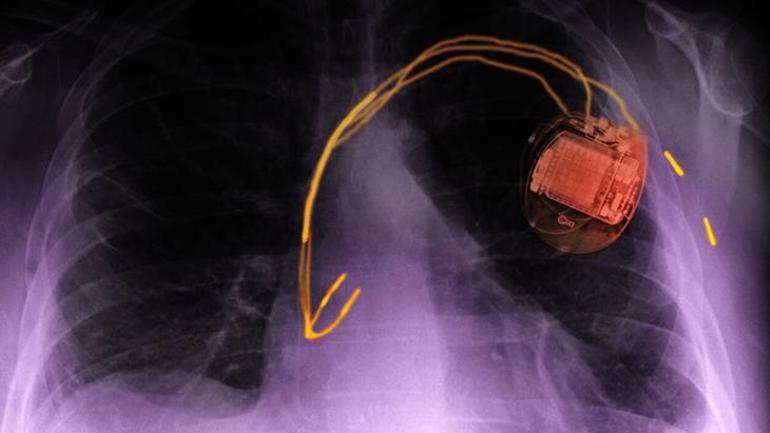

Kalp pilleri ve defibrilatörler kalp ritmi bozuklukları veya kalp yetmezliği olan hastaları tedavi etmek için kullanılan cihazlardır. Araştırmacılar, kalp pili ile ortalama yaşam süresinin 8,5 yıl olduğunu göz önünde bulundurarak dünya çapında kalp pili takan kişi sayısının 8 milyon ile 12 milyon civarında olmasının muhtemel olduğunu belirtiyor.

Elektrikli araçların şarj süresini kısaltmak için 350 kW’a kadar güç sağlayan yüksek güçlü şarj cihazları geliştirildi. Yeni şarj cihazları daha yüksek güç iletimi sağlayan DC (doğru akım) kullanırken, eski veya ev tipi şarj cihazları AC (alternatif akım) kullanır. Daha yüksek bir şarj akımıyla daha güçlü bir manyetik alan ve daha yüksek bir elektromanyetik girişim riski olabilir ve bu da bir kalp pilinin ritmi durdurmasına veya bir defibrilatörün uygunsuz bir şekilde ağrılı şok tedavisi vermesine neden olabilir.